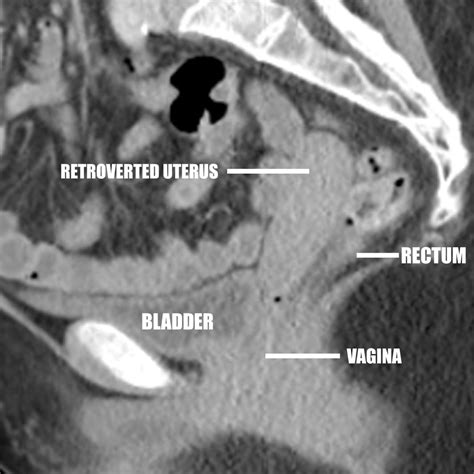

A retroflexed uterus, also known as a tilted uterus, is a condition where the uterus is angled backward towards the spine instead of forward towards the bladder. This condition is relatively common and is often discovered during routine gynecological examinations. It is important to understand that a retroflexed uterus is a normal anatomical variation and does not always cause symptoms or require treatment.

A retroflexed uterus is typically diagnosed during a routine pelvic examination. The healthcare provider may feel the uterus tilted backward during the exam. Additional diagnostic tests may include:

• Ultrasound: An ultrasound can provide a clear image of the uterus and its position.

• Magnetic Resonance Imaging (MRI): An MRI can provide detailed images of the pelvic organs.